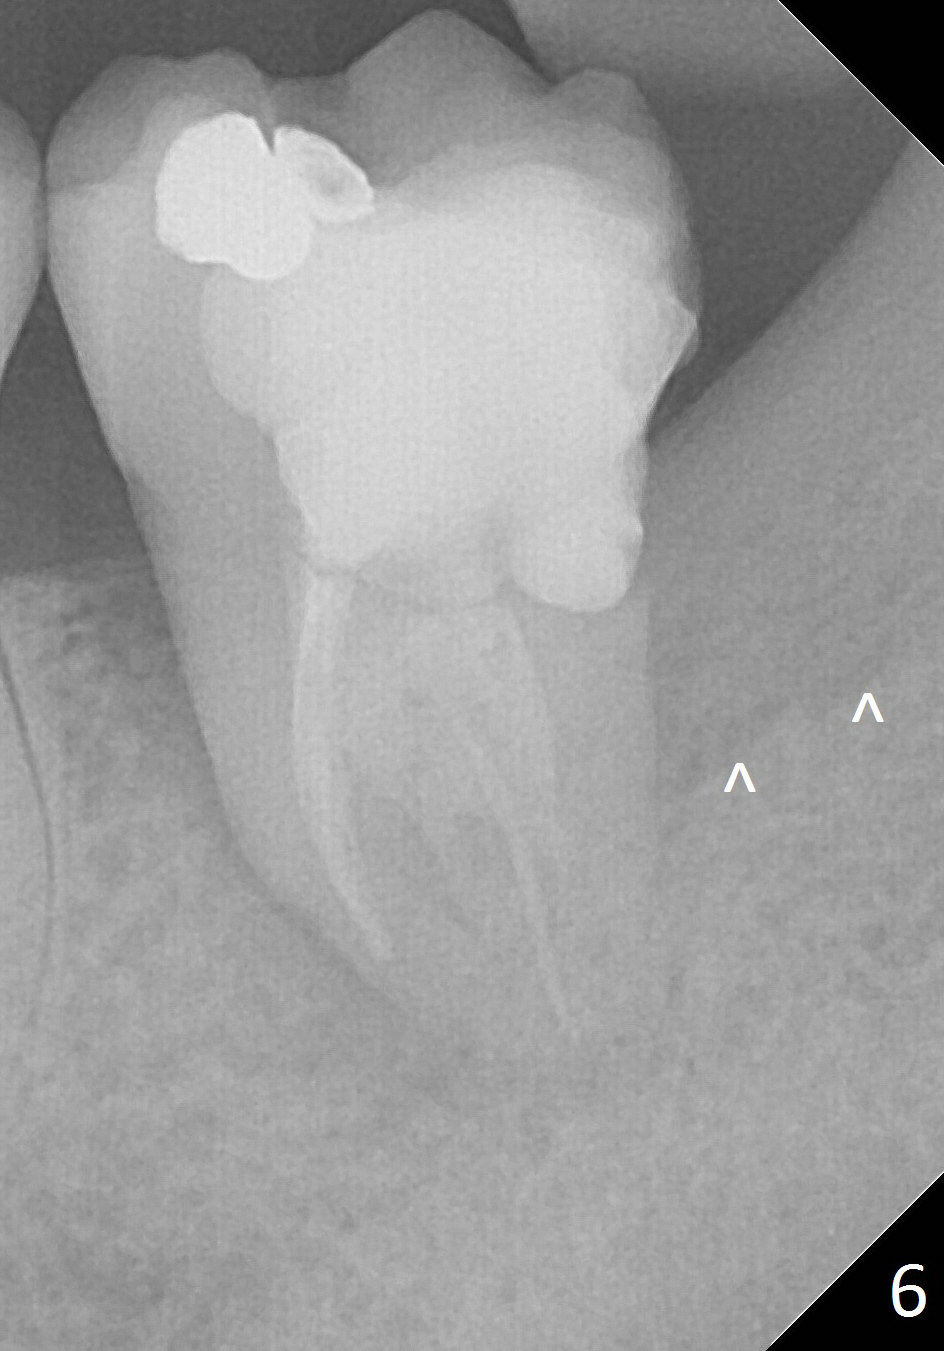

A 34-year-old man has distal deep caries of the lower 2nd molars. Root canal therapy turns out to be difficult on the right side due to bleach leakage. It would be also difficult to restore the distal defect. Finally he agrees to have extraction and implant. The result is good. He is ready to accept the same treatment for the left 2nd molar (Fig.1 (arrowheads: caries)). Metronidazole will be used for socket decontamination. Place a 5.9x10 mm bone-level implant 2 mm below the mesial crest (hopefully at the same level of the buccal crest) so that there is enough height to place an abutment (Fig.2). The apex of the implant is placed mesial to that of the root, since there is more bone, away from the superior border of the Inferior Alveolar Canal (red dashed line). The osteotomy is to be initiated in the middle of the mesial slope obliquely, more mesial (Fig.3 red line) than the center of the implant (green arrow). Once the lamina dura is penetrated, change the trajectory along the future long axis of the implant (Fig.4 red line). The depth will be 14 mm from the mesial gingival line (Fig.2). As the diameter of drills increases, the osteotomy tends to shift distal (Fig.5 pink arrow).

In fact, RCT is tried. Fourteen months later, the tooth remains symptomatic with mobility (Fig.6). Due to the distal defect caused by the 3rd molar (Fig.6,7 arrowheads), the implant should be placed as mesial and deep as possible.